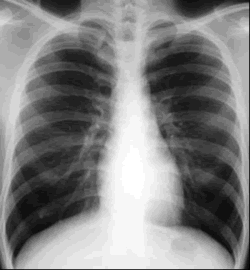

Chest

X-ray image.

One in three humans already carries the TB bacterium. |

|  | (Credit:

Image courtesy of University of New South Wales) | Although